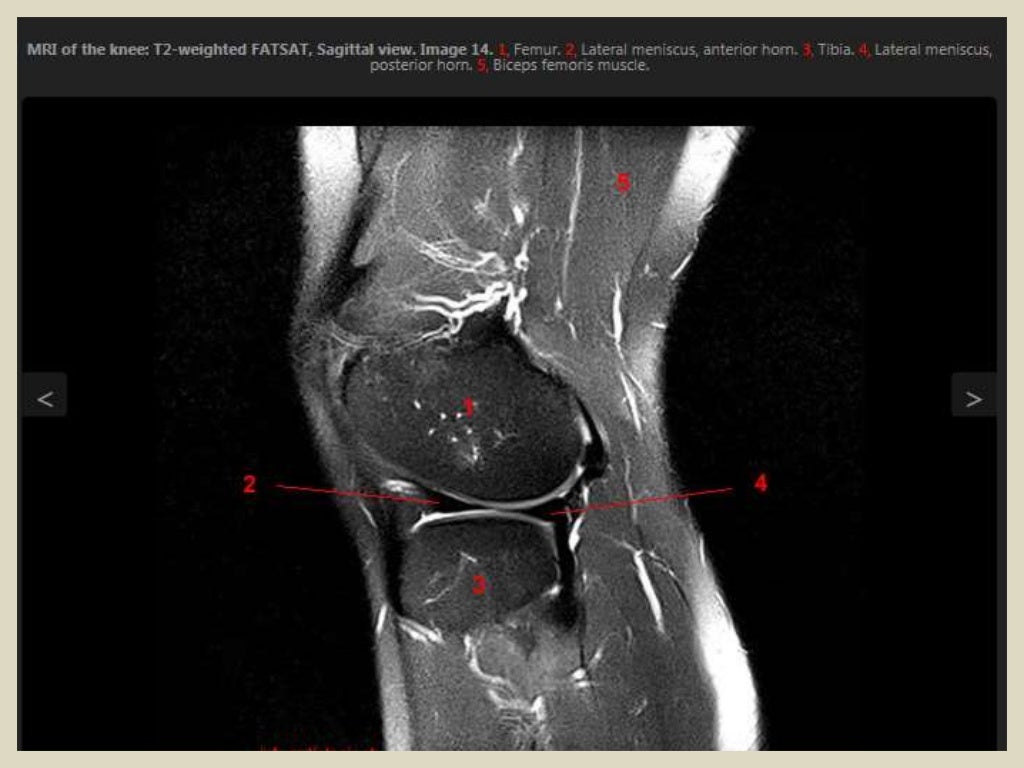

Здоровье колена: Параменисковая киста мениска